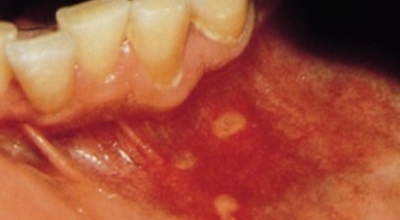

1. 구내염 원인 - 아프타성 구내염

입안 점막이 동그랗게 패여 통증을 유발한다면, 아프타성 구내염을 의심할 수 있어요. 음식을 먹을 때마다 아픈 작은 궤양이 생겼다면, 아프타성 구내염을 의심할 수 있답니다. 아프타성 구내염은 빨간색 둘레를 가진 둥근 형태의 흰색 궤양이, 얕은 깊이로 한 개 및 여러 개 생기며 통증을 동반하는 것이 특징입니다. 전 인구의 20~40%가 발병할만큼 통상적으로 나타나는 질환으로 20대, 주로 여성들에게 많이 나타나며, 일주일 정도면 자연적으로 치유되지만 1~3개월 간격으로 빈번히 재발하는 것이 특징입니다.

원인은 입 속 점막의 작은 상처나, 바이러스, 세균의 감염, 특히 수면 부족이나 과로, 스트레스가 쌓여서 면역력이 떨어졌을 때와, 비타민 B12 또는 엽산 결핍 시에 많이 생기 다고 알려져 있답니다. 흔한 질환이니만큼 자연적으로 치유 되지만, 통증을 동반하고, 궤양의 크기가 커지거나 숫자가 늘어나기도 하기 때문에 연고나 외용제, 가글액 등을 활용해서 증상을 경감시키는 치료를 하기도 해요.